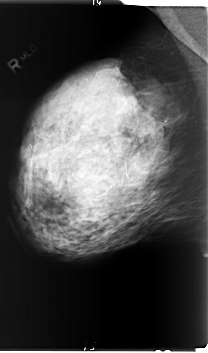

B_3006_1.RIGHT_CC

RIGHT_CC LINES 5936 PIXELS_PER_LINE 3792 BITS_PER_PIXEL 12 RESOLUTION 50 NON_OVERLAY